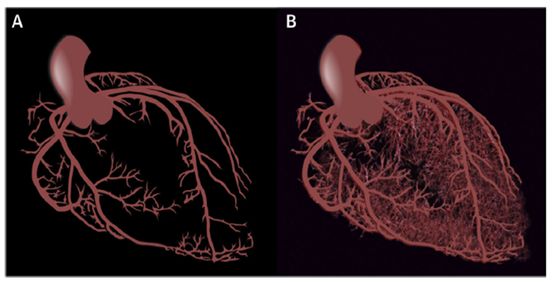

由前小动脉、小动脉构成的冠脉微循环造成了冠脉循环80%的阻力。你以为的冠脉循环也许是下图(A)的样子,但实际的冠脉循环由心外膜下冠脉和冠脉微循环共同构成,长下图(B)这样。